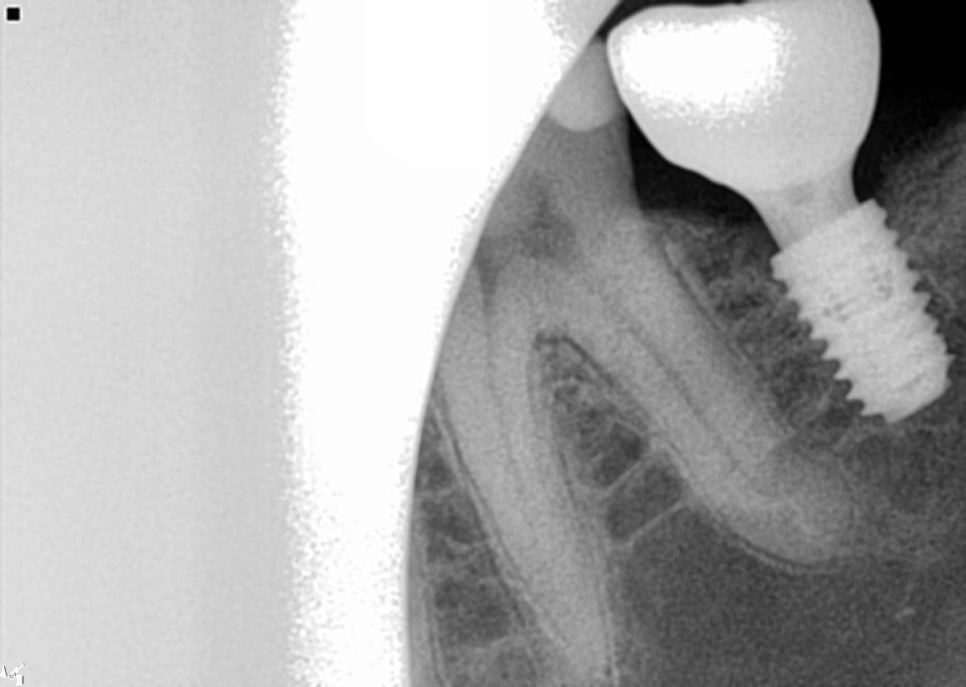

엑스레이 상에 보이는 것처럼 오른쪽 아래

#46 #47번은 힐링으로 지금 되어 있어

잇몸밖으로도 힐링이 보이고

#37은 커버스크류로 되어 잇몸 안에 있어

간혹 환자분들이 식립 후에 입안에서

안보이신다고 하시기도 합니다.

그래서 수술이 끝나고 엑스레이 촬영을 다시 하여

수술 성공 여부와 환자분께 확인시켜드리려

다시 한번 설명드리고 있습니다.

또한 치근단 촬영을 진행해 치아 전체적으로

주변 뼈를 자세히 촬영하여

여러 상태 확인을 합니다.

픽스쳐의 위치, 골유착여부, 보철물 체결 상태,

피개나 파절 여부를 확인했습니다.